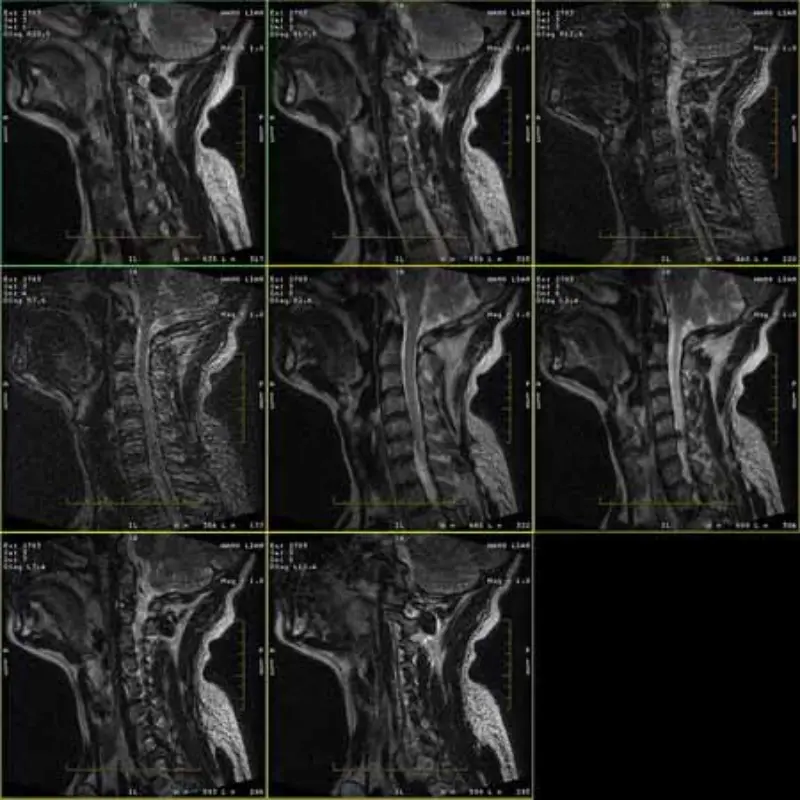

ຮູບພາບຂອງ FRFSE ແລະ GRE protocols ມີ ghost ແລະບາງຄັ້ງຮູບພາບ SNR ຕ່ໍາຈະປາກົດຢູ່ໃນຊຸດຫນຶ່ງ. ແຕ່ຮູບພາບໂປໂຕຄອນ SE ແມ່ນປົກກະຕິ.

ກະລຸນາເບິ່ງຮູບພາບທີ່ແນບມາ.